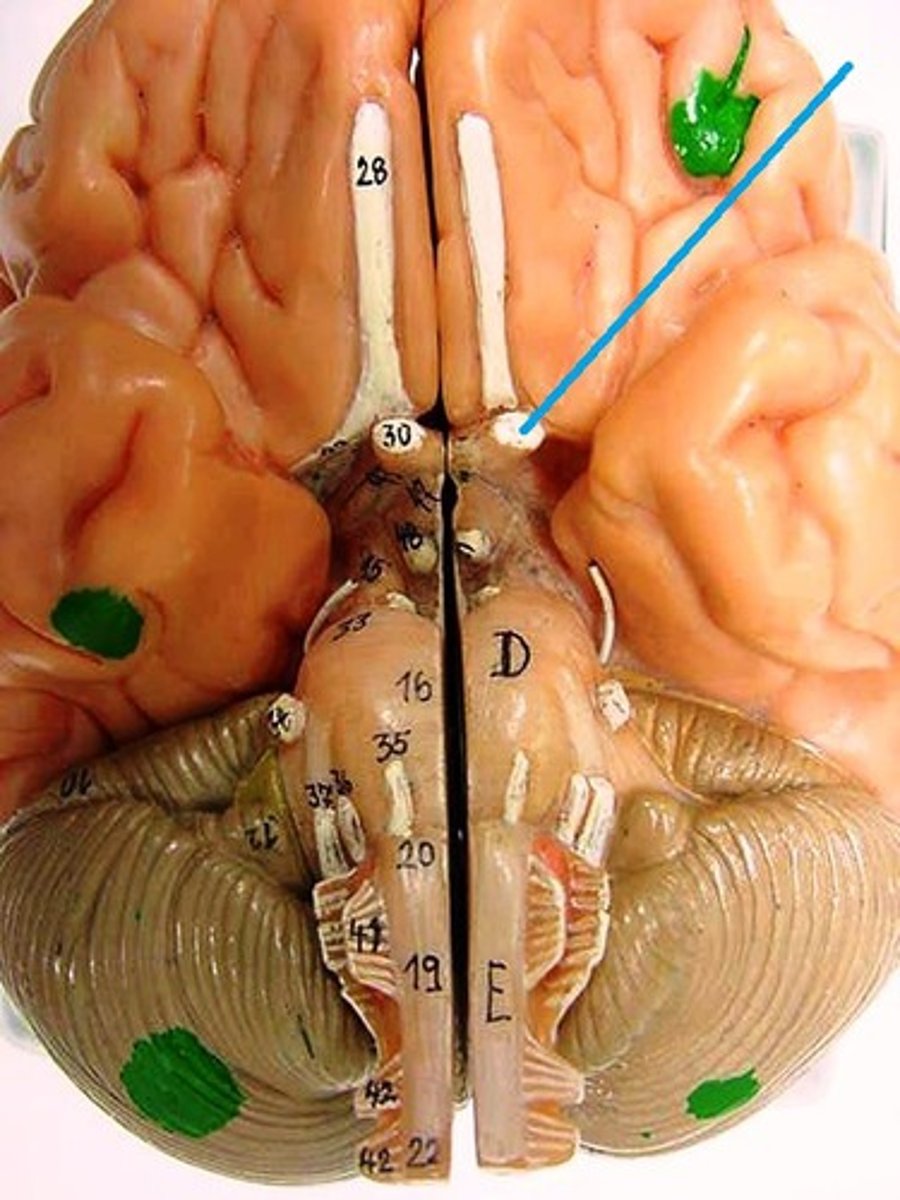

Olfactory Nerve

Function: special sensory- smell

Location: Telencephalon

Optic Nerve

Function: special sensory- vision

Location: Diencephalon

Oculomotor Nerve

Function: motor- eye movement; lid elevation, pupil contraction, lens shape

Location: Midbrain

Trochlear Nerve

Function: motor- eye movement (downward and inward)

Trigeminal Nerve

Function: mixed (motor, general sensory)- mastication, touch, pain, temperature

Location: Pons

Abducens Nerve

Function: motor- eye movement

Location: Medulla-Pons junction

Facial Nerve

Function: mixed (motor, parasympathetic, general sensory)- facial expression, lip articulation, taste on anterior tongue, secretion of saliva and tears

Vestibulocochlear Nerve

Function: special sensesory- hearing and balance

Glossopharyngeal Nerve

Function: mixed (motor, parasympathetic, visceral sensory, general sensory)- taste on posterior of tongue, gag reflex, swallowing

Location: Medulla

Vagus Nerve

Function: mixed (motor, parasympathetic, visceral sensory, general sensory)- visceral muscle movement (heart, lungs, intestines)

Accessory Nerve

Function: motor- movement of shoulders and neck

Location: Spinal cord

Hypoglossal Nerve

Function: motor- speech movements of the tongue, swallowing